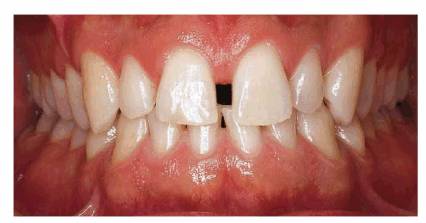

One of the most challenging tasks of modern restorative dentistry is resolving

the dilemma of spaces between anterior teeth. The presence of a diastema can be

a problem because the esthetic value of anterior spacing varies between

cultures, and the best treatment options are often rejected. To some, an

anterior diastema is desirable, whereas others attempt to hide it with habits

such as lip or tongue posturing.6 Some patients have even resorted

to daily applications of wax or cotton to disguise a diastema (Figures 23-1A

and B).

Figure 23-1A and B: Some patients resort to daily applications of materials such as wax (#25) or cotton (#10) to disguise a diastema.